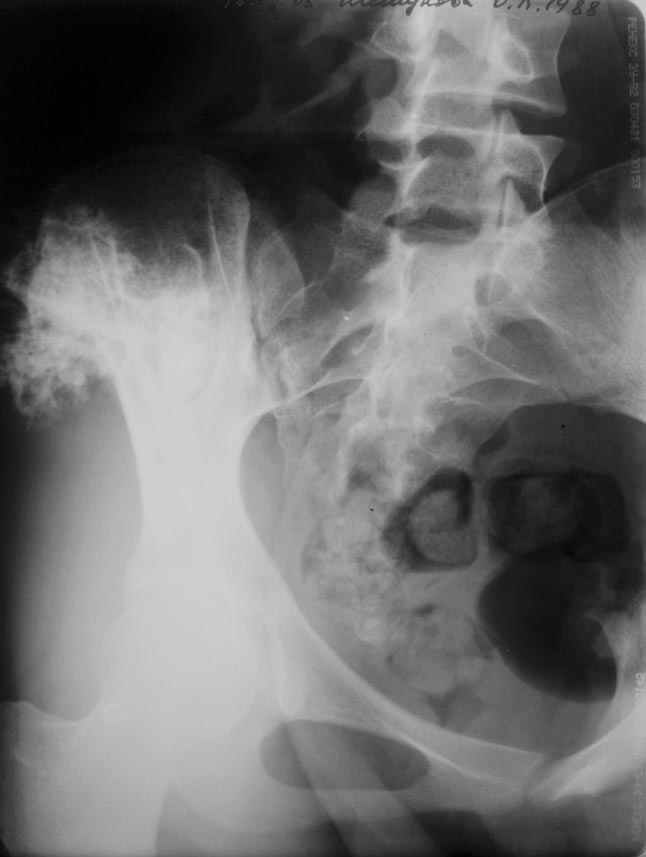

Уважаемые коллеги! К нам поступила пациентка 16 лет с диагнозом: остеохондрома крыла правой подвздошной кости.

Учитывая большие размеры образования, необходимо удаление его с резекцией крыла подздошной кости вместе с ее гребнем. Предполагается наличие большого дефекта. Поделитесь опытом закрытия таких дефектов.

Судя по КТ, проблема не в гребне а в крыле...

Опухоль имеет задне-наружное нправление...

По-моему, КТ-картина наводит на мысль об озлокачествлении (резкая неоднородность, местами размытие контуров) - вторичной хондросаркоме. Местами, кстати, имеется рост и в направлении брюшной полости. Для решения вопроса об объеме резекции в данном случае оправдана трепанобиопсия. Если это хондросаркома, особенно низкодифференцированная, то стоит обсудить возможность удаления всего крыла с окружающими мягкими тканями. Вариант реконструкции - комбинированная пластика аллотрансплантатами. А вот какими - зависит от наличия костного банка и возможностью индивидуального изготовления трансплантатов. При отсутствии таковой не лучше ли направить ее в ЦИТО?